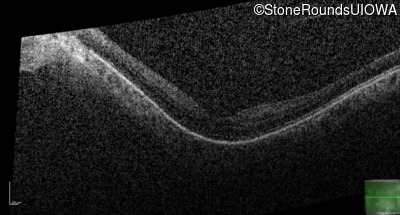

Optical Coherence Tomography - Left - 20/25 +2

Exemplar / OCT Stack